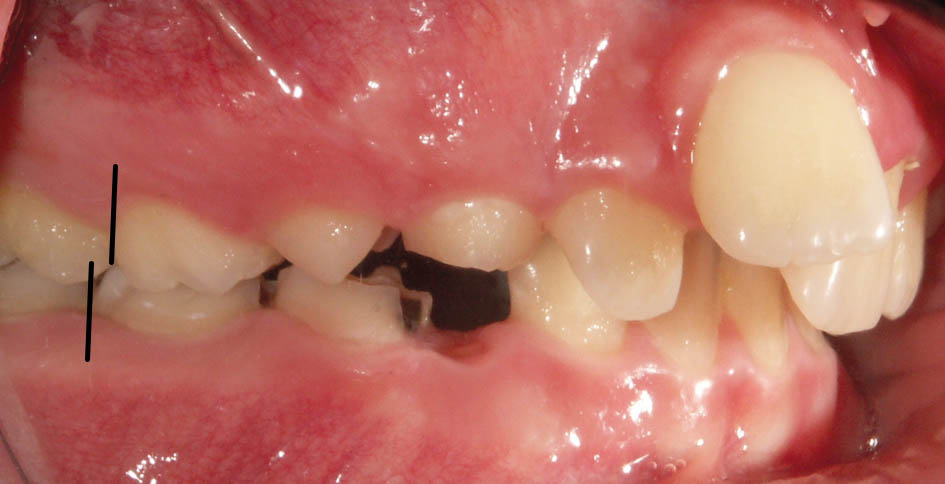

درشکل78-5 و79-5 رابطه مولری یک کاسپ کامل کلاسII است و بعد از پروترود شدن قدامیهای بالا به کمک براکتها (شکل80-5) مندیبل هم حدود 3mm جلوتر قرار گرفته است.

شکل 78-5: بیمار یک کاسپ کامل کلاسII و دیپ بایت شدید است.

شکل 79-5: نمای روبرو کمبود اورجت را نشان میدهد.

شکل 80-5: پروترودشدن قدامیهای بالا باعث حذف فشار دیستاله روی مندیبل گشته و مندیبل جلوتر قرار میگیرد.